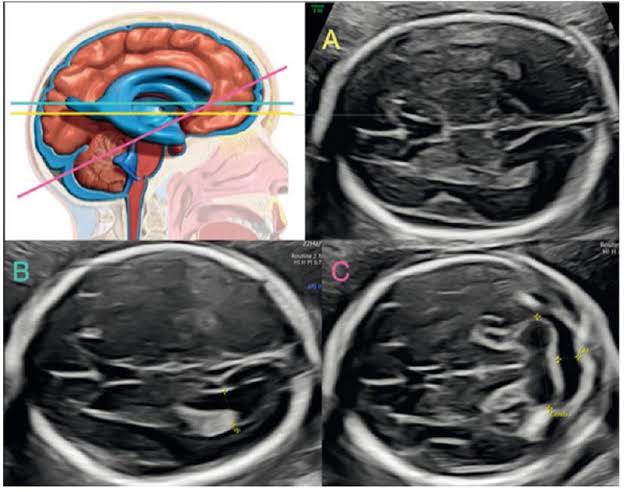

Neurosonografía Fetal

Estudio detallado, avanzado y especializado del sistema nervioso central y cerebro del bebé para descartar anomalías neurológicas con alta precisión.